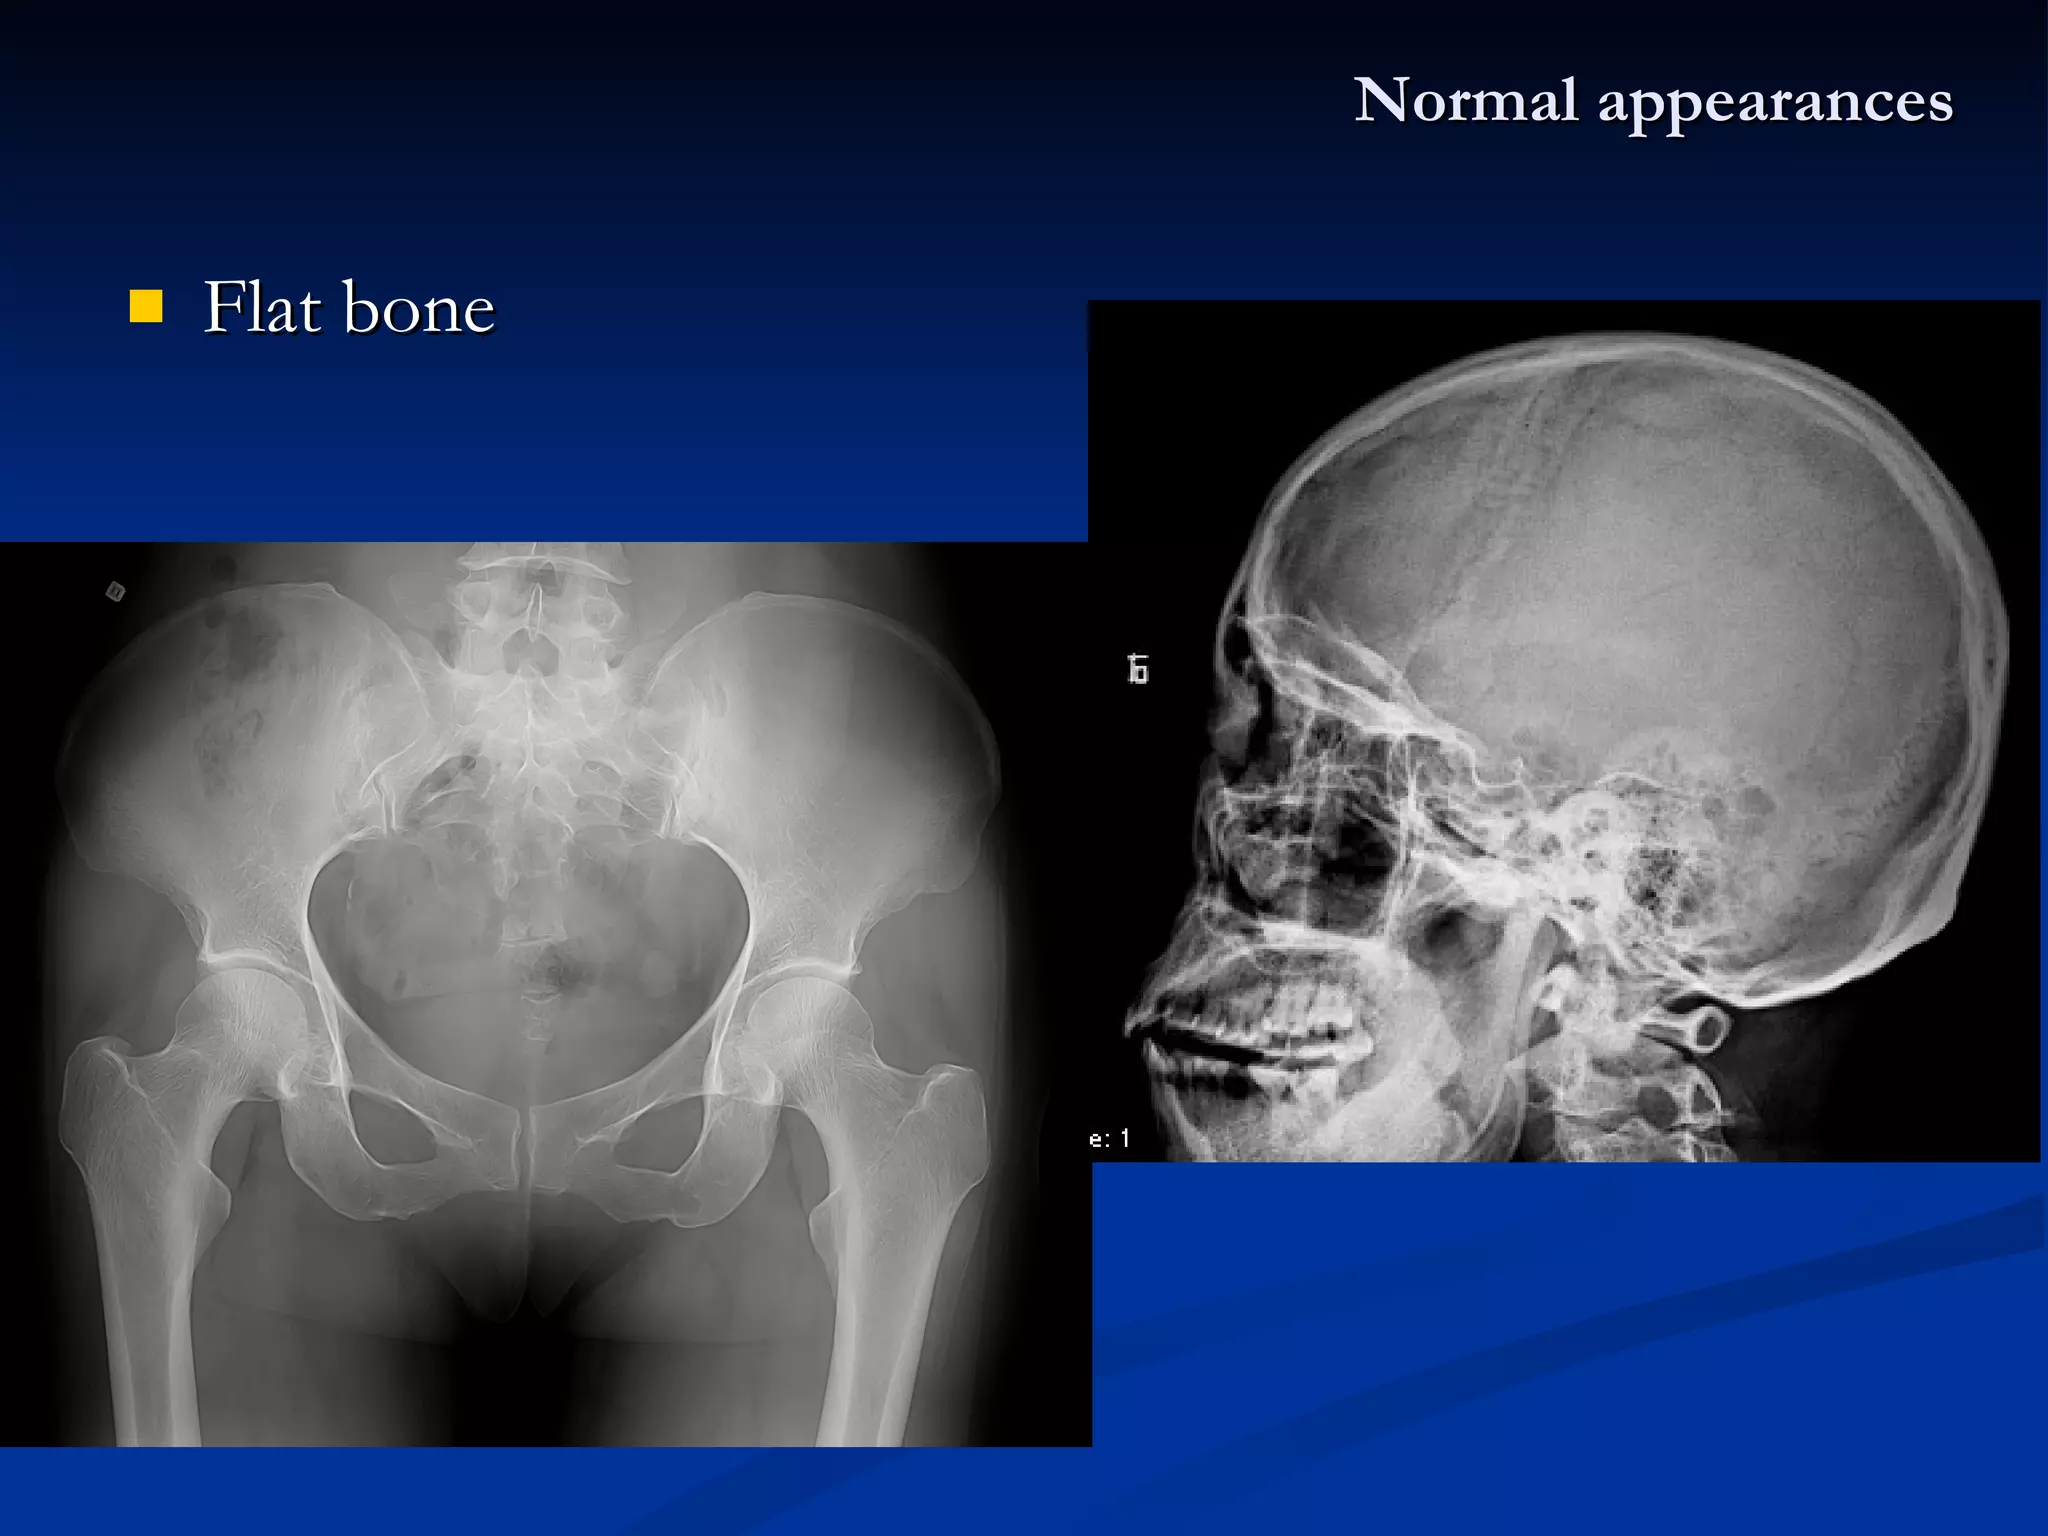

Normal X-ray appearances The types of skeleton: Long bone Pediatric  : diaphysis 、 metaphysis 、 epiphysis 、 epiphyseal plate Adult  : diaphysis (shaft) 、 Short bone Flat bone  –  hematopoiesis Irregular bone Joint

Flat bone Normal appearances